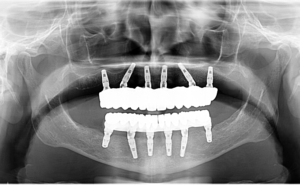

După o evaluare detaliată a stării dentare și o discuție despre sănătatea generală, Dr. Cazacu Corrado a propus un plan de tratament format din reabilitare orală cu ajutorul a 6 implanturi dentare la maxilar și 6 la mandibulă. Scopul nostru a fost nu doar să îi redăm funcționalitatea dentară, ci și să o ajutăm să recâștige încrederea pierdută.Planul detaliat a inclus:- Extracția dinților compromiși

- Inserarea a 12 implanturi dentare

- Dantură fixă provizorie, la aproximativ 24 de ore de la inserarea implanturilor dentare, pe care pacienta a purtat-o timp de 6 luni.

- După cele 6 luni a sosit momentul mult așteptat: fixarea lucrărilor definitive!

În radiografia atașată mai jos puteți observa radiografia pacientei, ajunsă deja la etapa lucrărilor finale: